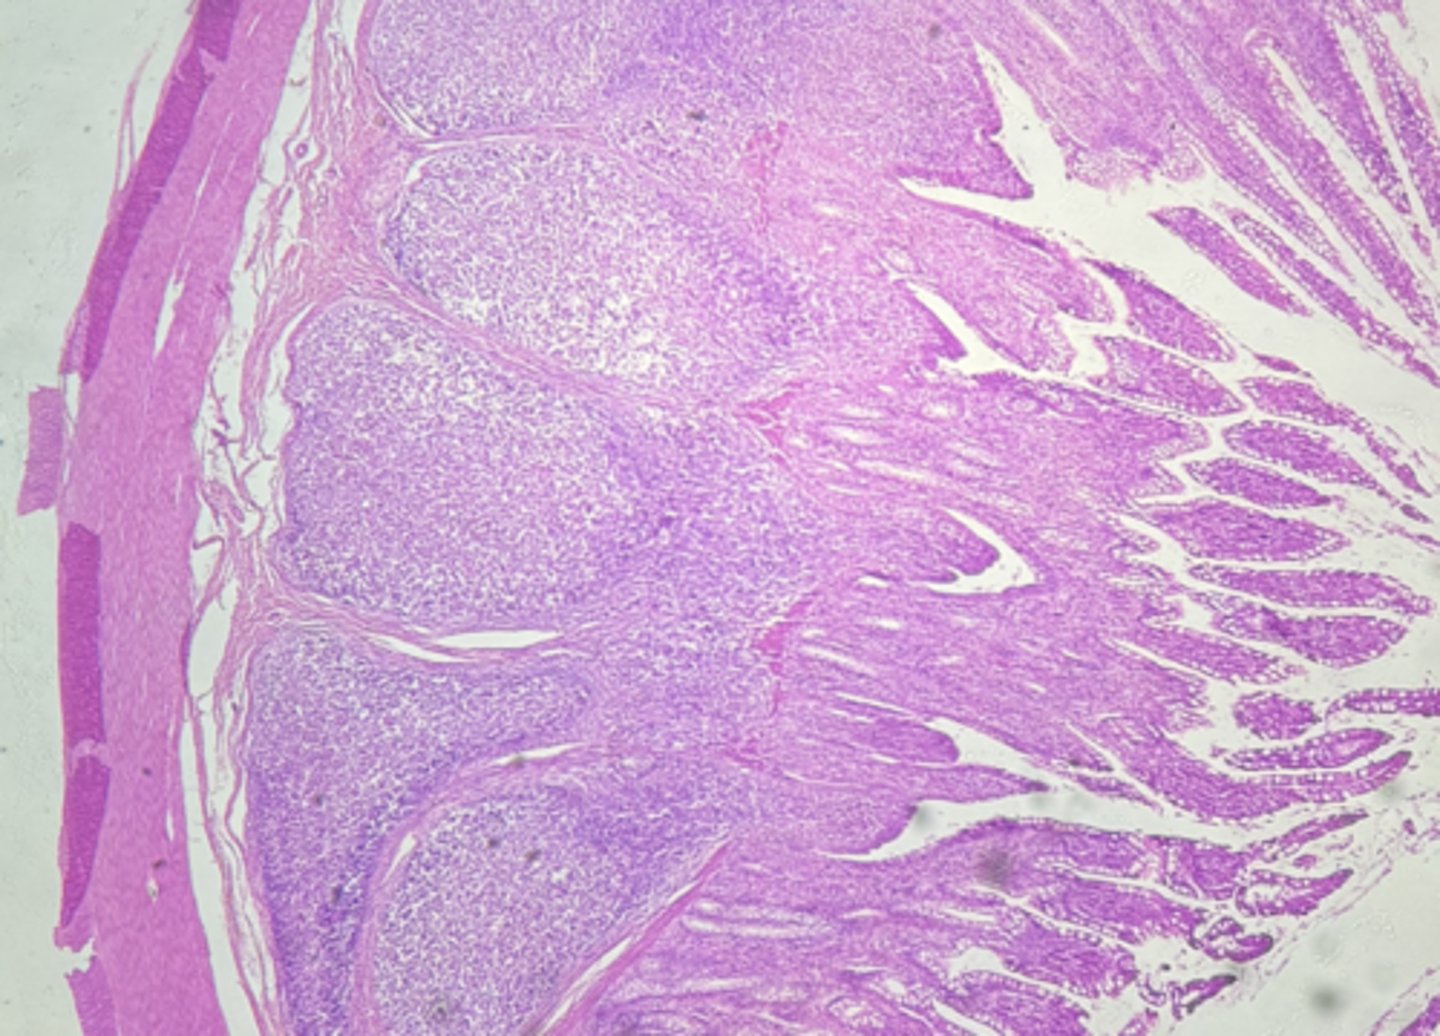

A- Esophagus

B- Stomach

Name the Tissue A & B